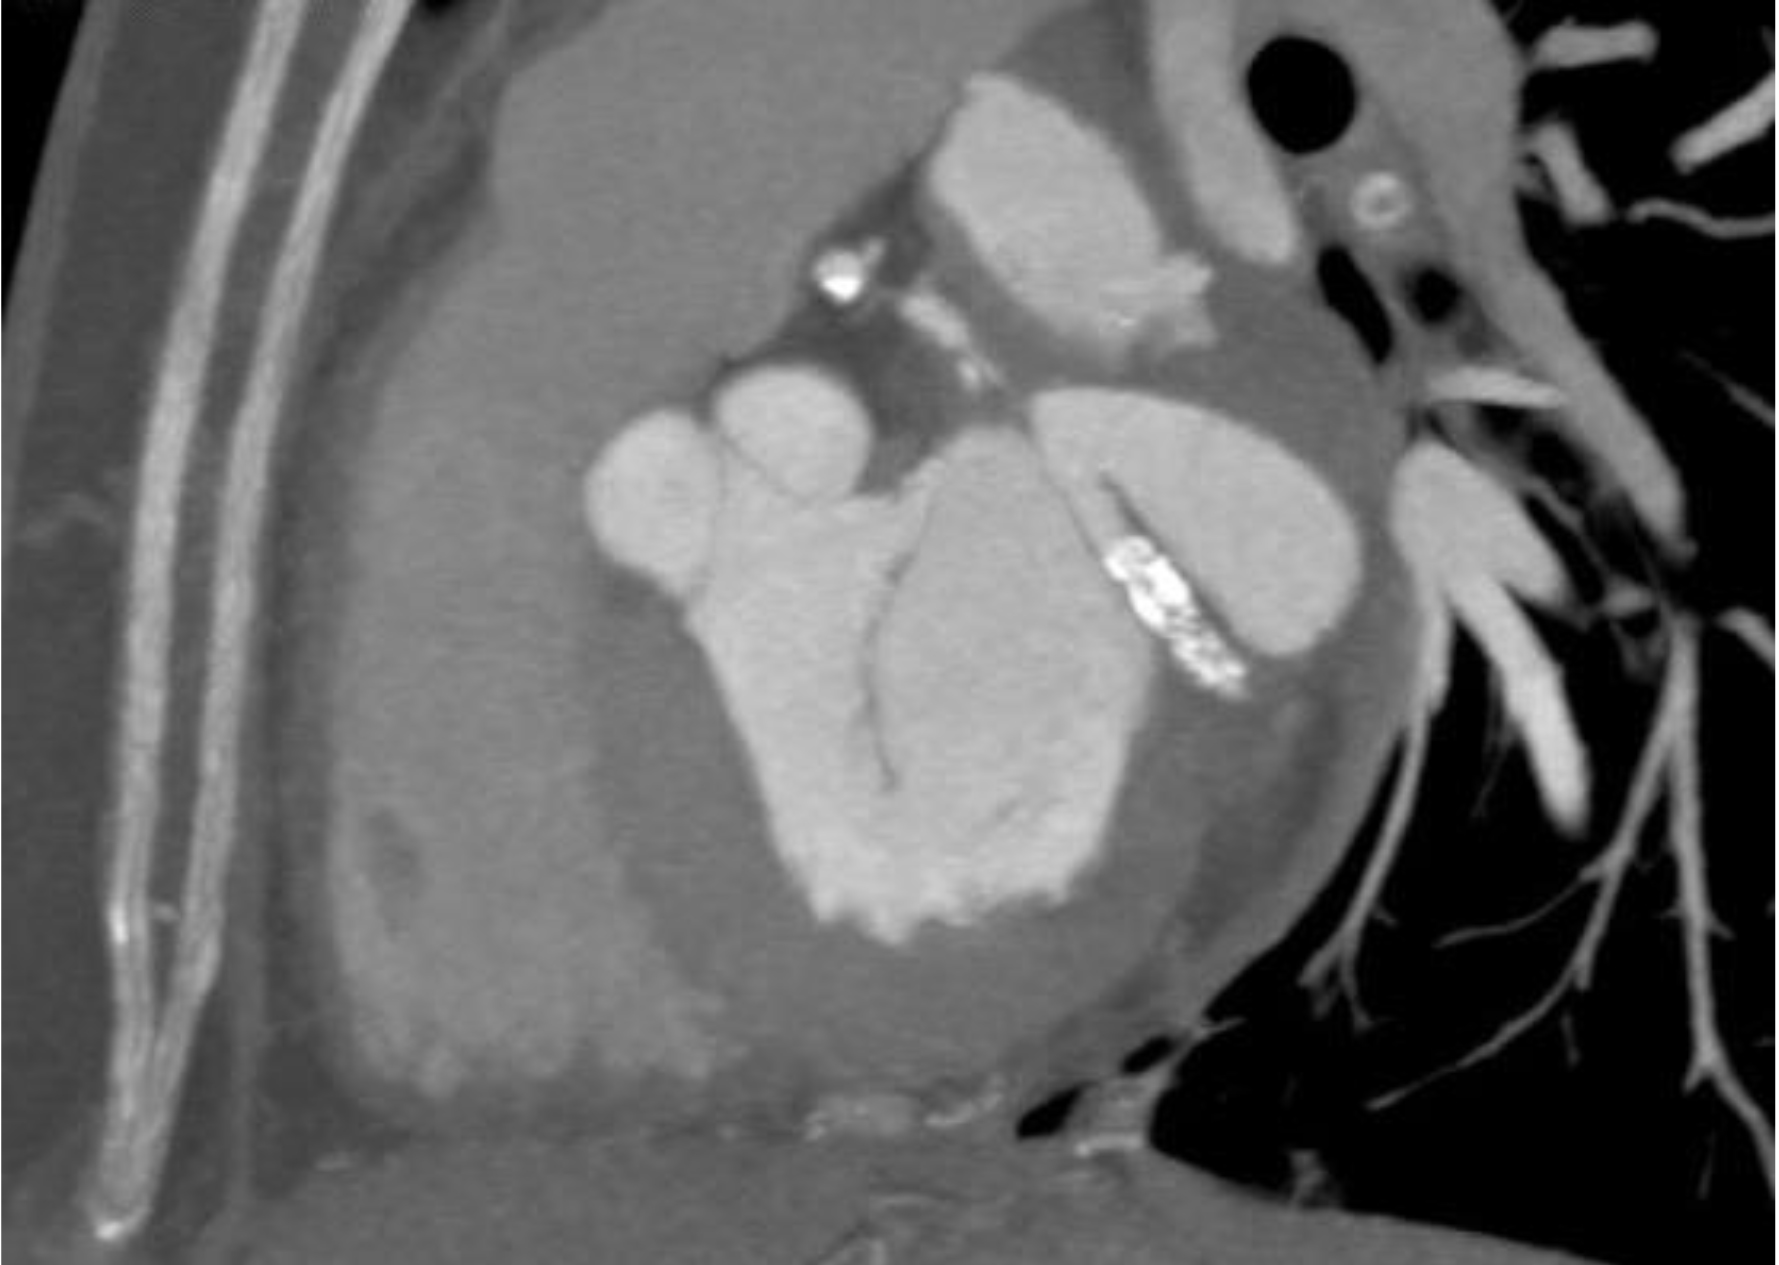

For the better anatomic orientation of the aneurysm, the patient was subjected to Computed Tomographic Coronary angiography, which revealed the aneurysm size to be of 3.5X3.5 cm with thrombus in situ, there was a predominance of calcified stenosis in the second obtuse marginal branch (OM2) (Figure 3). Because of the large pseudoaneurysm, infective etiology was ruled out after two sets of blood culture showed no growth over 48 hours.

Figure 3: Computed tomography image showing the pseudoaneurysm and calcified lesion within the stent in the circumflex artery.